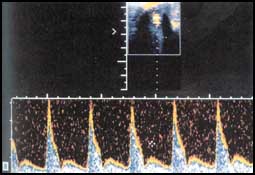

3- وأخيراً قد يلزم إجراء الأشعة الصوتية مع الدوبلر الملون الذي يقيس كمية الدم المتدفق الى القضيب بدون او بوجود الأدوية الموسعة للشرايين التي يمكن حقنها في القضيب نفسه. وبالتالي يستطيع الطبيب دراسة حركة الدم داخل أوعية القضيب ومعرفة التشخيص ووضع العلاج المناسب.